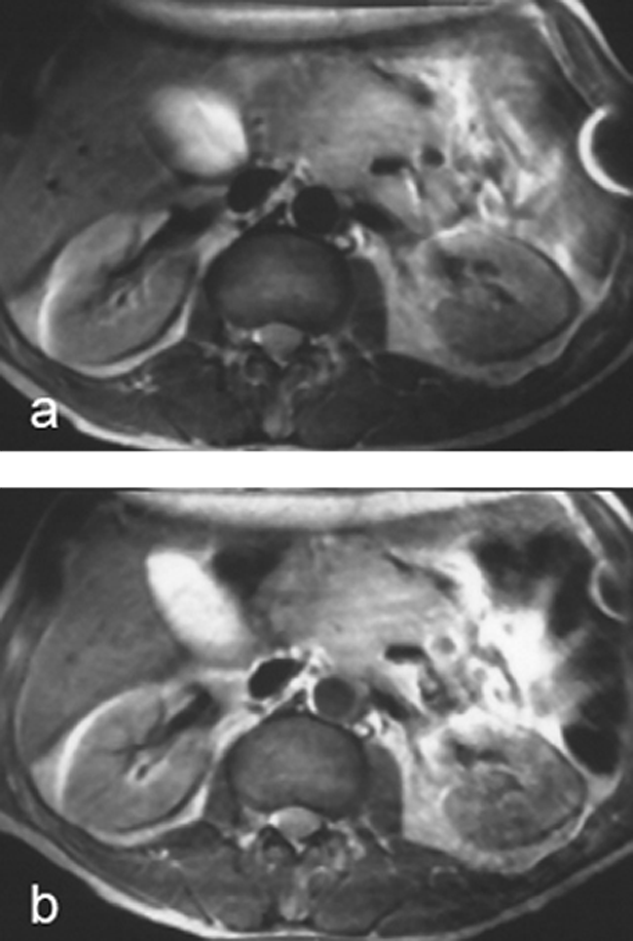

Figure 13-19:

Intermediately weighted images of the up­per abdomen. Recurrent mesenteric tumor.

(a) plain; (b) after ingestion of a negative oral contrast agent. On the enhanced ima­ge, the contour of the tumor is well de­li­ne­ated from the neighboring liver and in­tes­ti­nes.

Artifact created by ECG lead in the left ab­do­mi­nal wall.